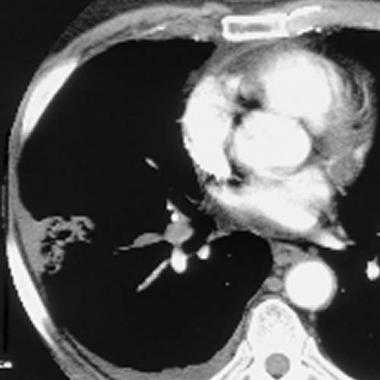

Массивная двусторонняя ТЭЛА у мужчины 79 лет с острым коронарным синдромом. При КТА удалось выявить тромбы, не полностью перекрывающие кровоток в главных ветвях легочной артерии, а также в верхне- и нижнедолевой и сегментарных ветвях легочной артерии. На обзорной рентгенограмме грудной клетки патологические изменения отсутствовали.